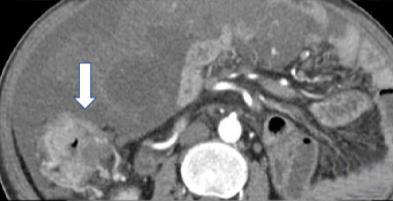

• 计算机体层摄影血管造影在腹腔镜结肠癌根治术前评估中的应用效果

2025, 31(6):24-31. DOI: 10.12235/E20240177

摘要 (181) HTML (147) PDF 4.65 M (171) 评论 (0) 收藏

摘要:目的 分析计算机体层摄影血管造影(CTA)在腹腔镜结肠癌根治术前评估中的应用效果。方法 回顾性分析2021年1月-2024年2月于该院接受腹腔镜结肠癌根治术的120例患者的临床资料。其中,60例行常规腹部CT和CTA,60例行磁共振成像(MRI)。以术后病理为金标准,判断CTA对临床T分期与术后病理的一致性,以及评估肿瘤是否侵犯肠系膜血管和周围组织的准确度。结果 术前CTA诊断T分期的准确率为95.00%(57/60),一致性好(Kappa = 0.925,P < 0.05);术前MRI诊断结肠癌T分期的准确率为98.33%(59/60),两者比较,差异无统计学意义(χ2 = 0.26,P > 0.05)。CTA预判肿瘤是否累及肠系膜上动脉、肠系膜上静脉、肠系膜下动脉、肠系膜下静脉、腹主动脉、肾动脉、肾静脉和脾动脉等血管,与术后病理的一致性好。特别是在预测肠系膜血管受累方面,CTA的敏感度为94.44%,特异度为95.83%,准确度高达95.00%。结论 对于行腹腔镜结肠癌根治术的患者,术前CTA不仅能清晰地显示结肠癌T分期,还能揭示肠系膜血管的走行和变异,以及肿瘤与周围组织的关系和侵犯程度,从而为手术规划提供强有力的支持,确保了腹腔镜手术的安全性,减少了不必要的手术风险。